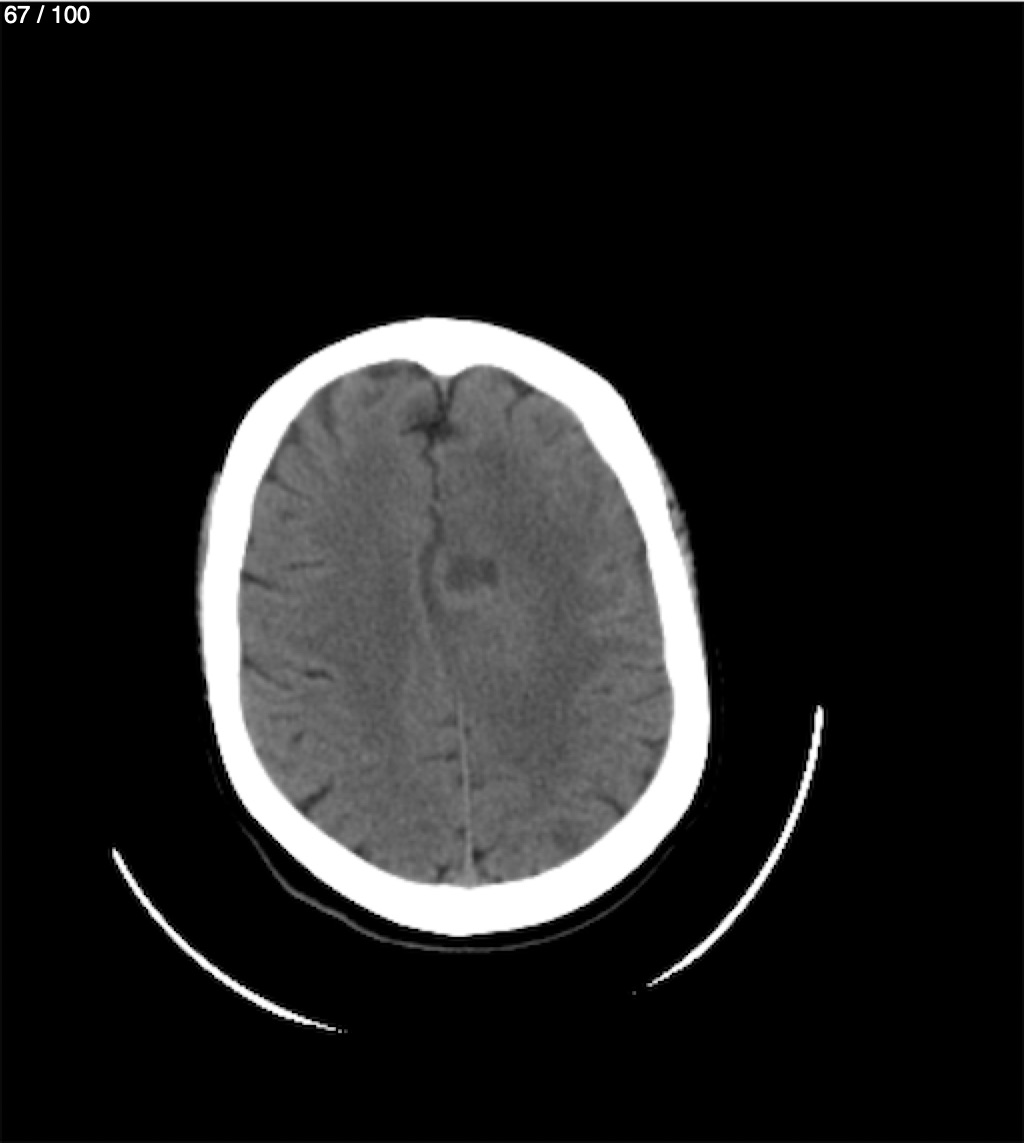

Valentin Perez Gomez 69A - T.C Craneo